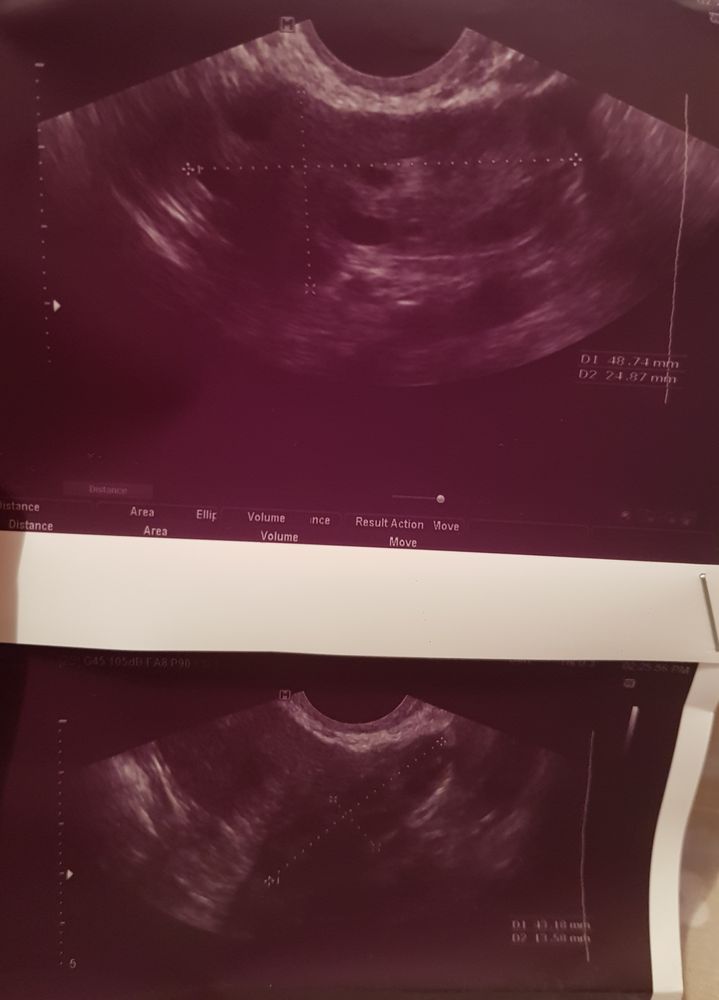

На 1ой ФМ врач сказала, что в правом яичнике видит ЖТ (11 ДЦ), а в левом ДФ 15 мм.

На 2ой ФМ так же ЖТ в правом (14 ДЦ), но в левом уже не видит ДМ...

При всём при том про ЖТ нигде в заключении не сказано. Последний цикл был 35 дней, до этого менструации нормальной не было (СПКЯ).